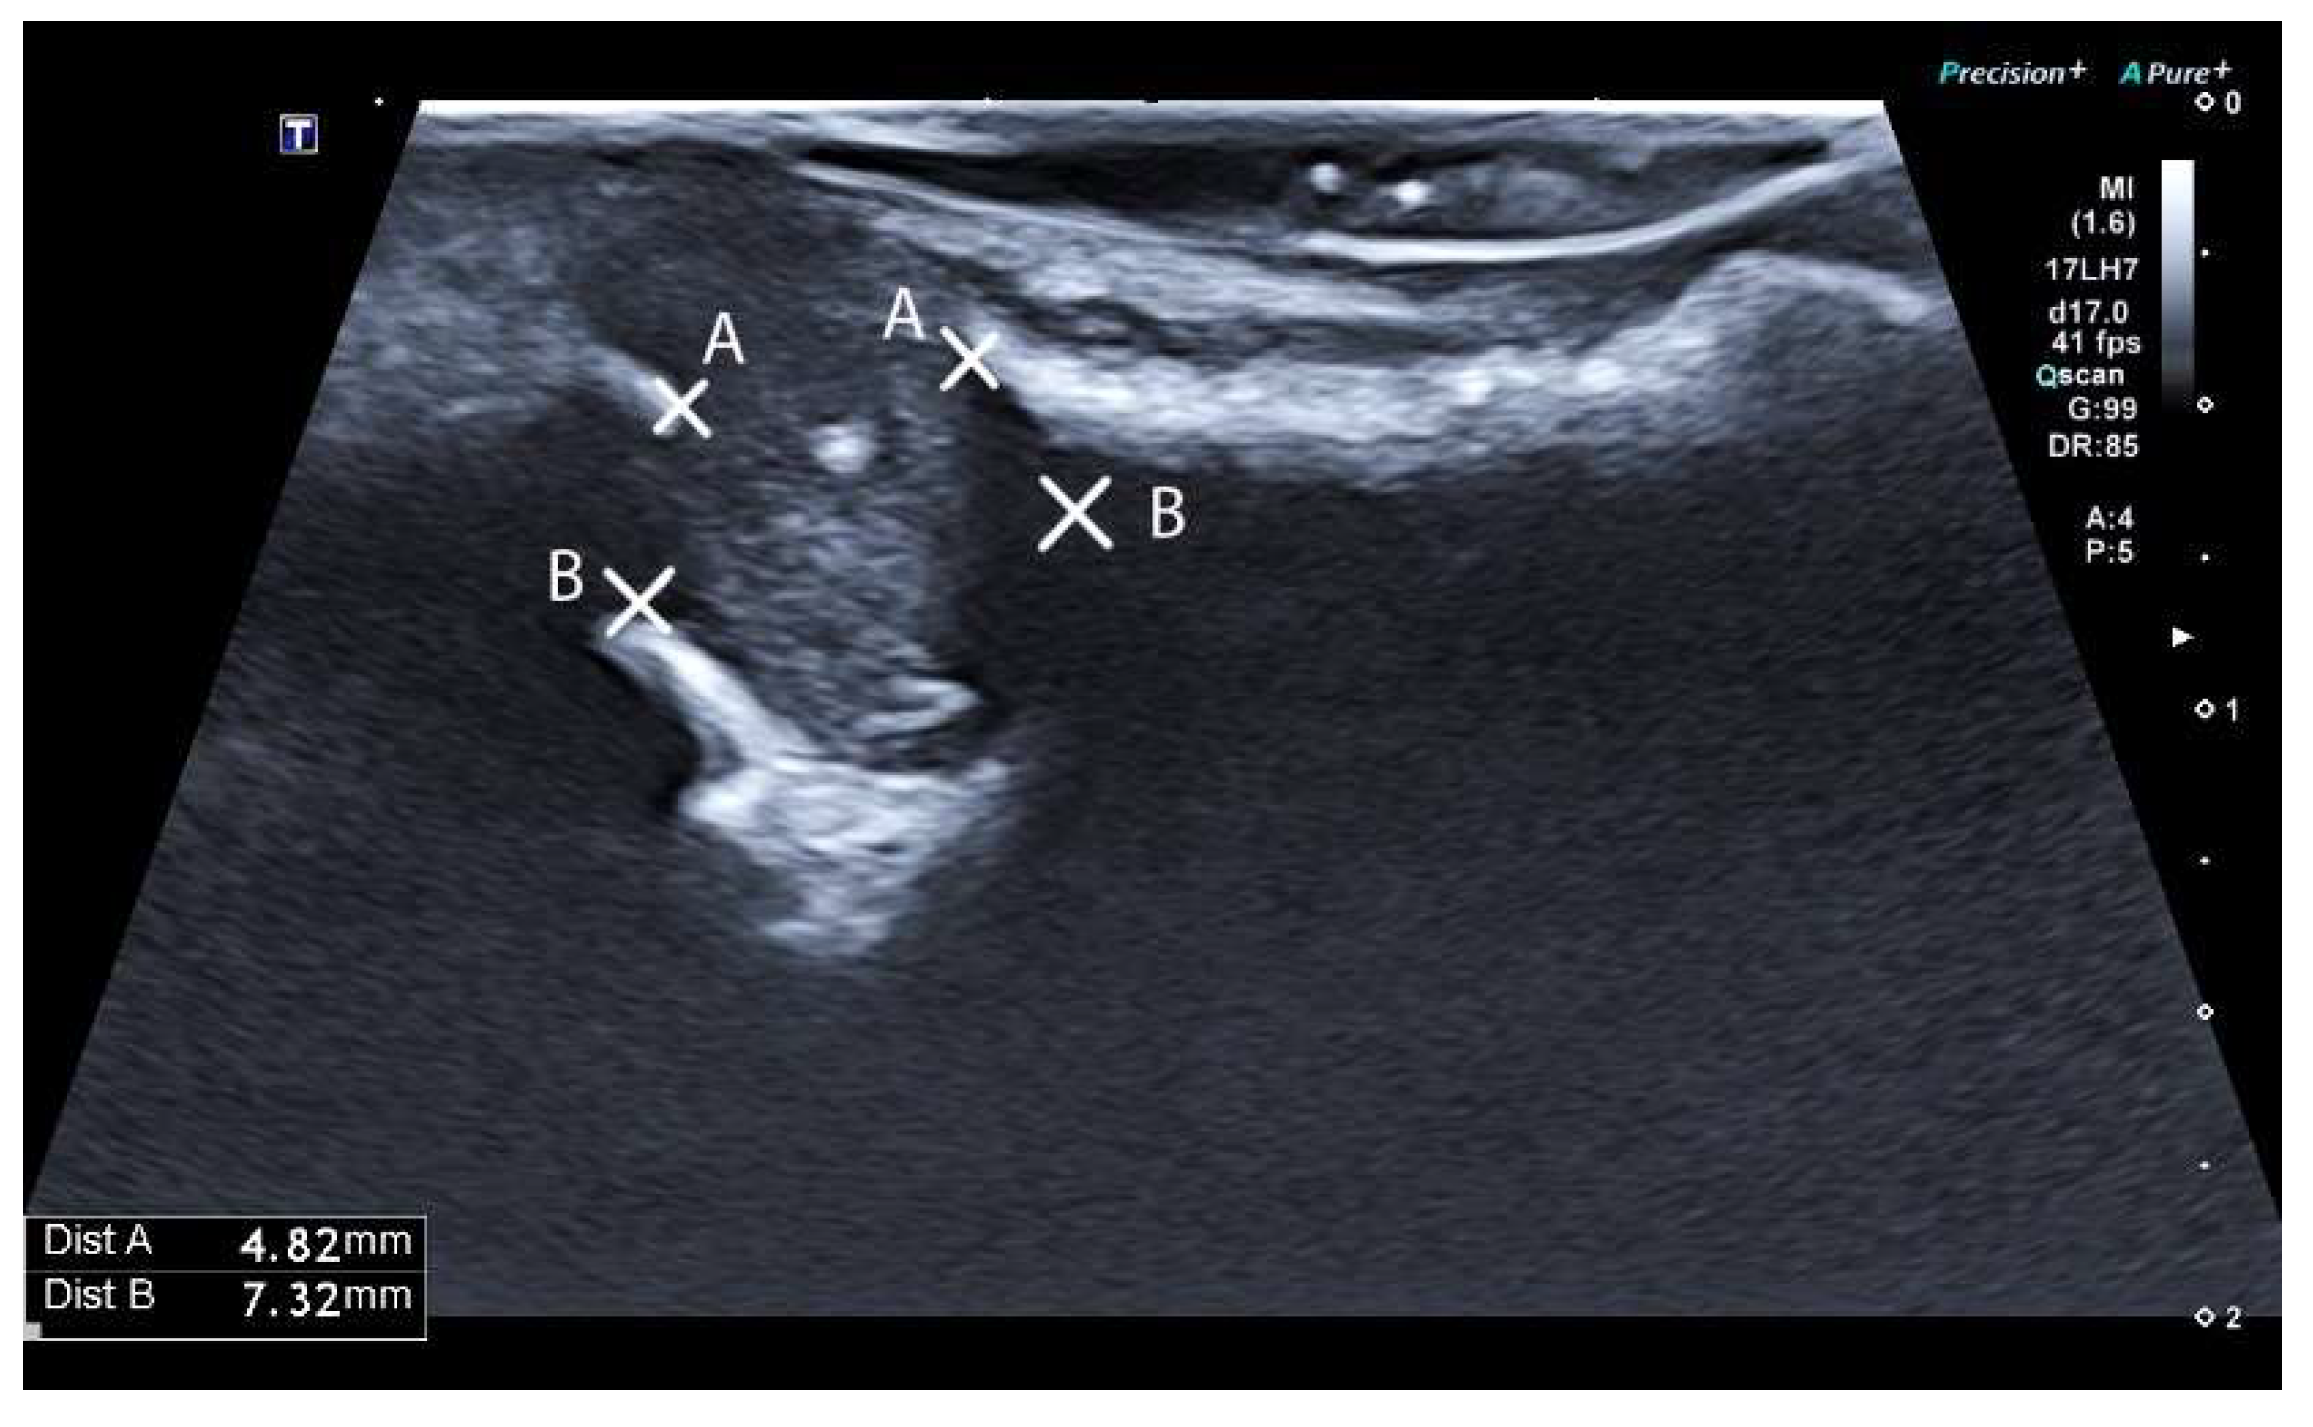

2.3.3. Ultrasound Examination and Evaluation